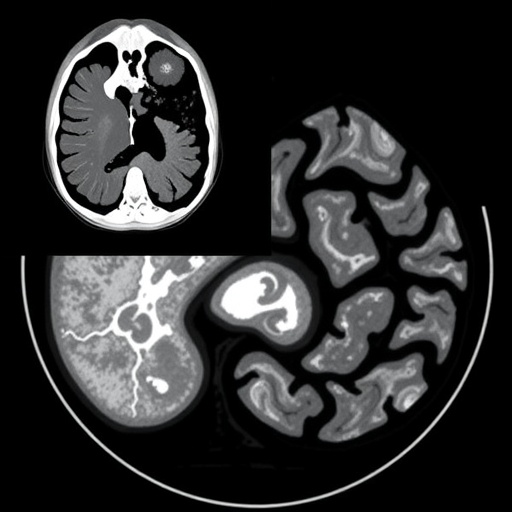

Solid pseudopapillary neoplasms are uncommon exocrine pancreatic tumors, representing less than 3% of all pancreatic neoplasms. Predominantly affecting young women in their third decade, these tumors characteristically exhibit low malignant potential. The presented case involved a 31-year-old female patient who experienced progressive right-upper quadrant abdominal pain. Subsequent imaging revealed an exceptionally large mass measuring approximately 12.5 by 9 by 8 centimeters, located in the head of the pancreas, demonstrating a lobulated contour with solid and cystic elements intermixed with coarse calcifications—an uncommon feature in SPN pathophysiology.

Radiologic assessment employed contrast-enhanced computed tomography (CT) and magnetic resonance imaging (MRI) to elucidate tumor characteristics. Imaging depicted a well-encapsulated heterogeneous lesion that abutted but did not infiltrate adjoining organs or major vascular structures. Intriguingly, tumor markers such as carcinoembryonic antigen (CEA) and carbohydrate antigen 19-9 (CA 19-9) remained within normal parameters, casting further doubt on malignancy and reinforcing the suspicion of SPN, which often manifests without elevation of traditional pancreatic tumor markers.

Surgical intervention entailed a cephalic pancreaticoduodenectomy, commonly known as the Whipple procedure. The choice of complete surgical resection reflects current consensus that this remains the gold standard for treatment, even for large tumors demonstrating extensive calcification. Resected specimens revealed a tumor with mixed solid and cystic architecture, areas of hemorrhagic degeneration, and striking coarse calcifications amidst hyalinized fibrous stroma, which histopathological examination extraordinaire highlighted.